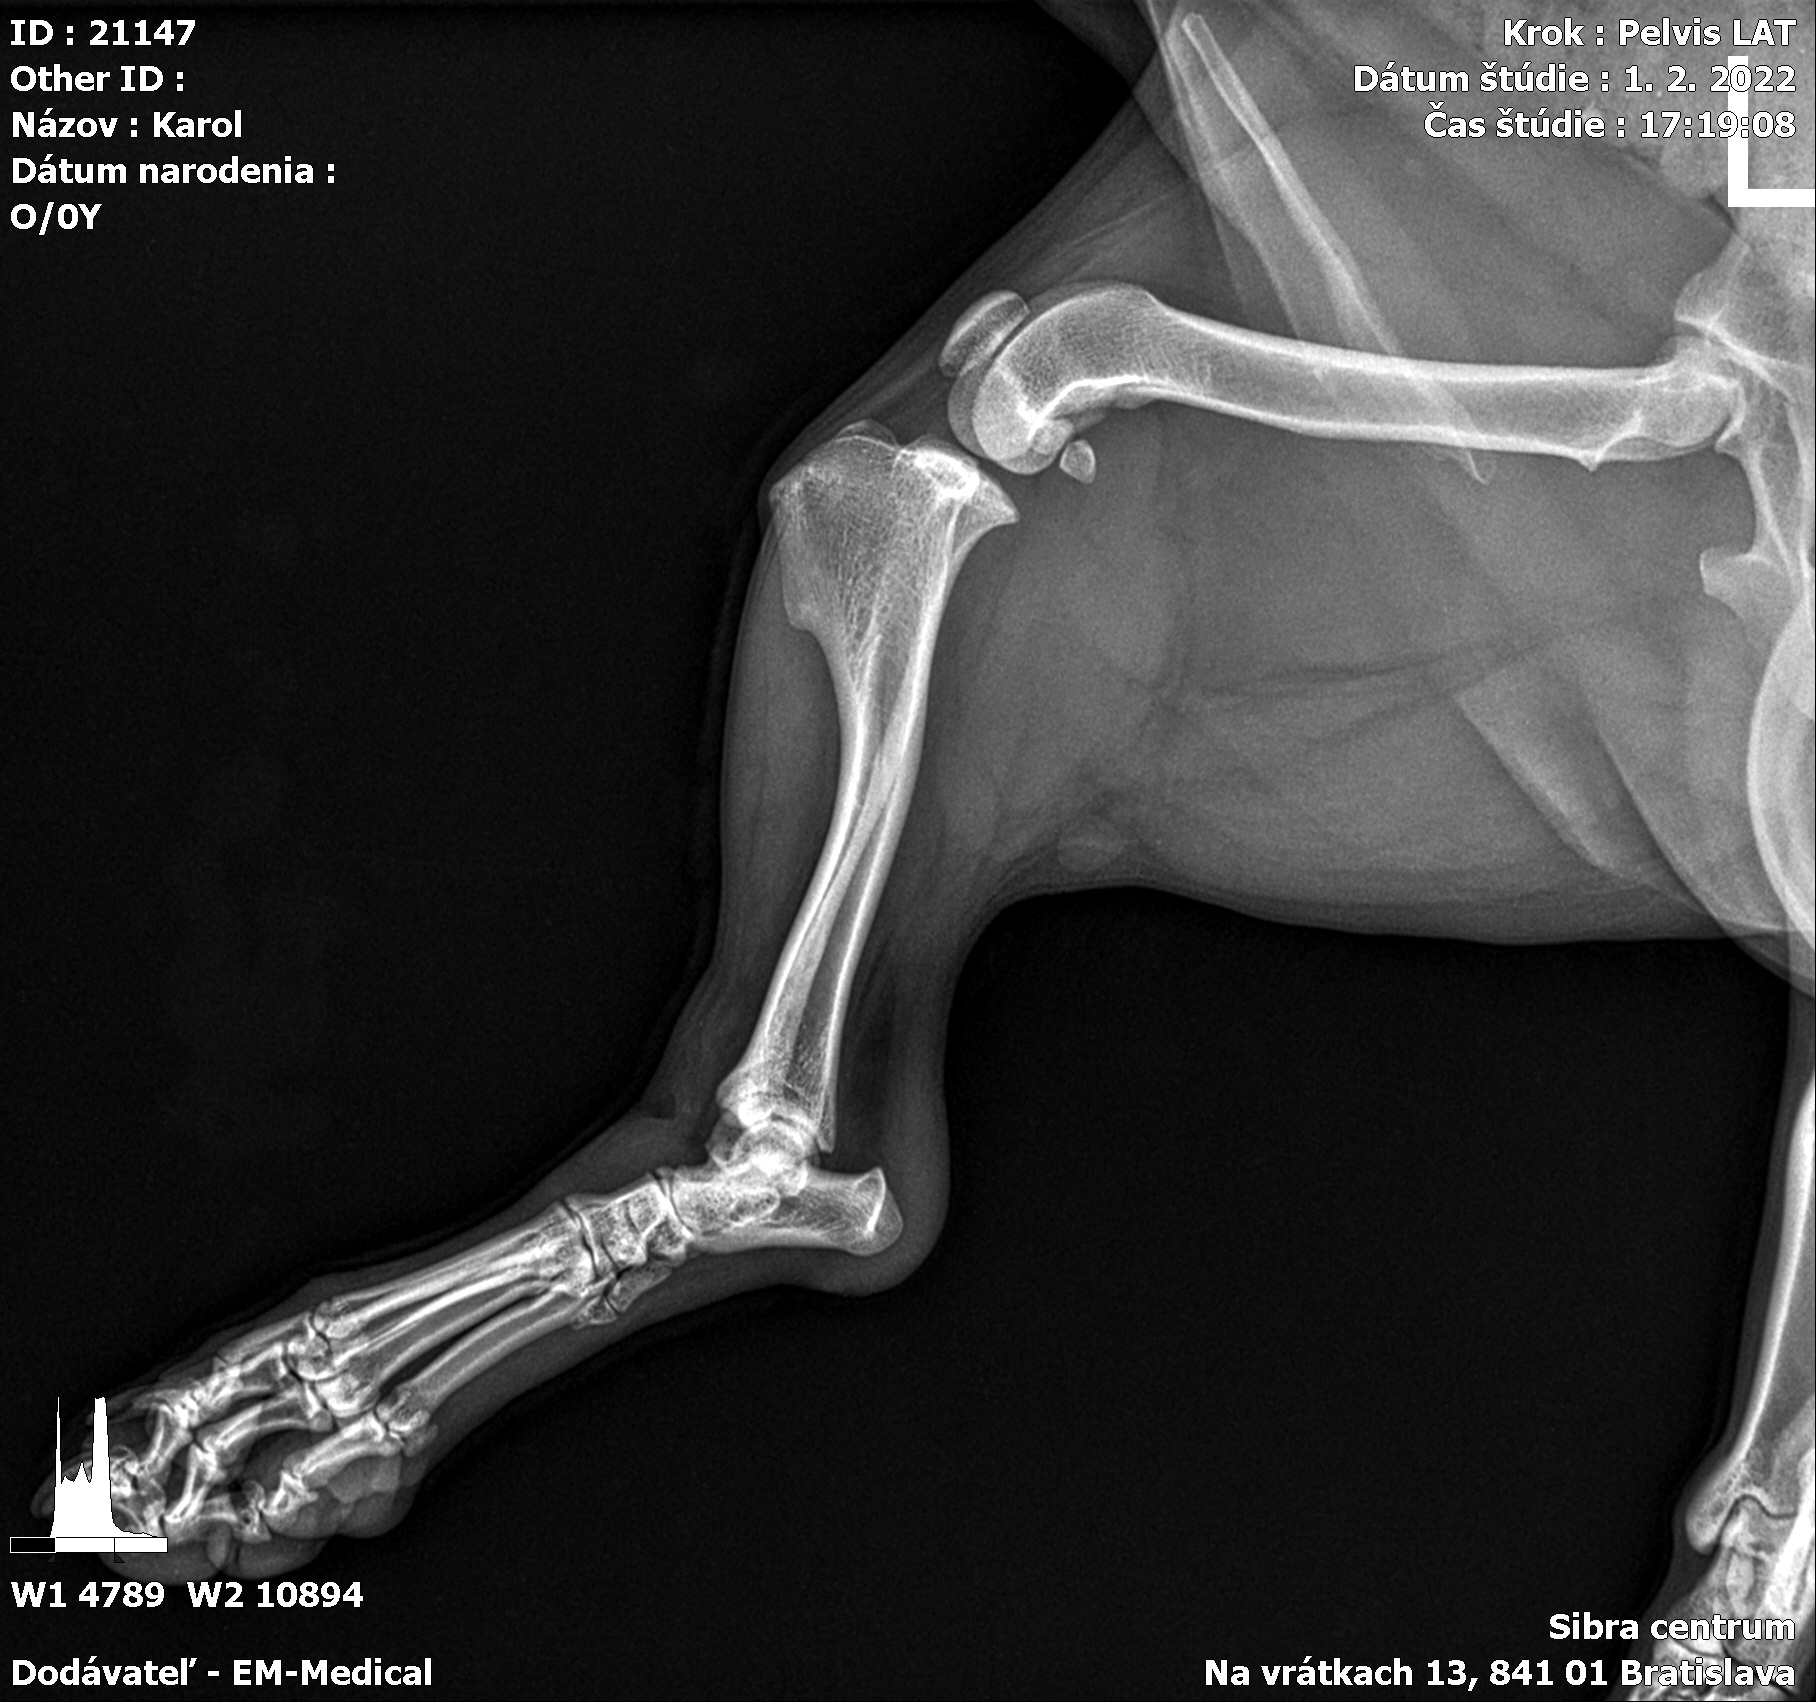

Karola nám doviezla pani, ktorá ho našla, asi jediná dobrá duša, ktorá pri ňom neprešla so zatvorenými očami. Ihneď sme s krpcom utekali na veterinu aby sa zistila závažnosť jeho zranení. Hneď pri prvých RTG snímkoch sa ukázala obojstranná fraktúra panvy, taktiež fraktúra krídla panvy a keby mu to chudákovi nestačilo, do tretice sa objavila zlomenina stavca. Karolko mal neznesiteľné bolesti, ale krásne prečkal vyšetrenie lebo vedel, že je v dobrých rukách a dostáva sa mu pomoci. Po nálezoch sme okamžite kontaktovali neurológiu a ortopédiu na veterinárnej klinike Sibra - centrum veterinárnej medicíny, kde sme dostali hneď termín na príjem.